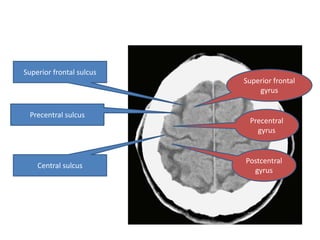

Superior frontal sulcus Superior frontal gyrus Precentral sulcus Precentral gyrus Postcentral Central sulcus gyrus